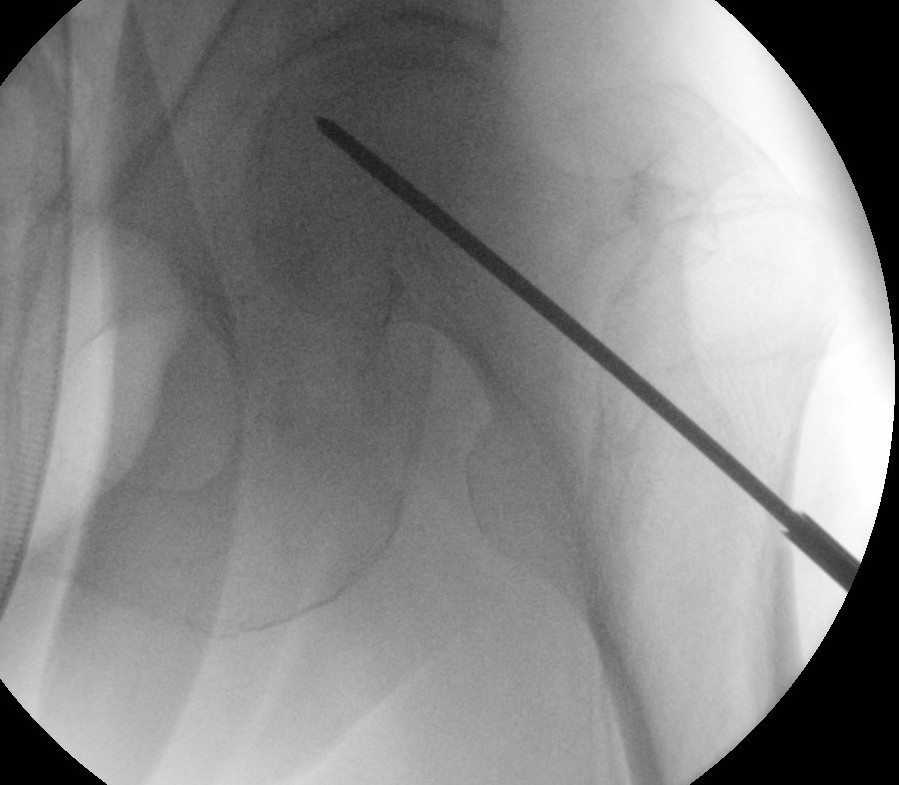

Technique

- AP and lateral xray

- entry point through greater trochanter

- above lesser trochanter to reduce fracture risk

- enter site of AVN

- overdrill

- +/- bone graft / vascularized bone graft / tantalum rod / BMAC (bone marrow aspirate concentrate)